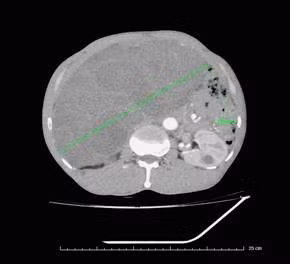

Khối u sau khi cắt bỏ trọng lượng 5kg. Sau mổ người bệnh được theo dõi, điều trị sát. Bệnh nhân ổn định, phục hồi tốt và xuất viện ngày thứ 7 sau phẫu thuật.

Khối u sau khi cắt bỏ trọng lượng 5kg - Ảnh BVCC